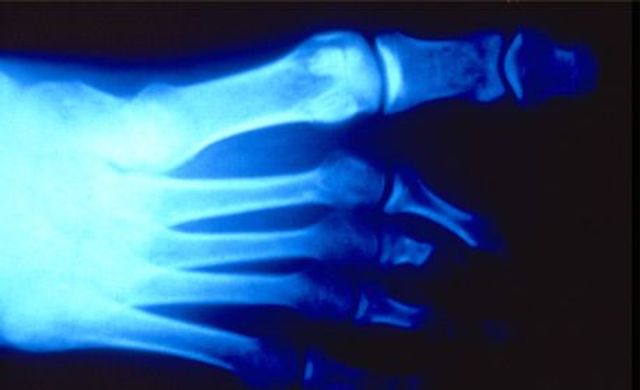

Dokumente des Grauens: Röntgenaufnahmen von Folteropfern

Hermann Vogel: Fotos von Folteropfern sind oft so brutal und direkt, dass der Betrachter reflexartig wegschaut. Anonyme Röntgenbilder sind besser auszuhalten. Zunächst erkennt der Betrachter nur, dass ein Finger fehlt oder ein Knochen zerbrochen ist. Das weckt sein Interesse und er will erfahren, was dem Menschen passiert ist. Die Bilder führen also dazu, dass sich die Menschen mit dem Thema Folter beschäftigen – auf erträgliche Weise. Und genau das ist mein Ziel.

Sie entlarven von außen nicht erkennbare Verletzungen, somit auch Spuren von Folter. Eine gerichtsmedizinische Untersuchung macht Frakturen, eingeführte Fremdkörper, Nadeln sichtbar. Die Aufnahmen ermöglichen eine Plausibilitätsprüfung. Stimmen die Schilderungen des Opfers mit dem Verletzungsmuster überein? Stimmt das Alter der Verletzung überein mit dem Zeitraum, den die Person für die erfahrene Folter angibt? Entspricht die Foltermethode dem, was für die angegebene Region und die verantwortliche Organisation, Militär oder Miliz, bekannt ist?